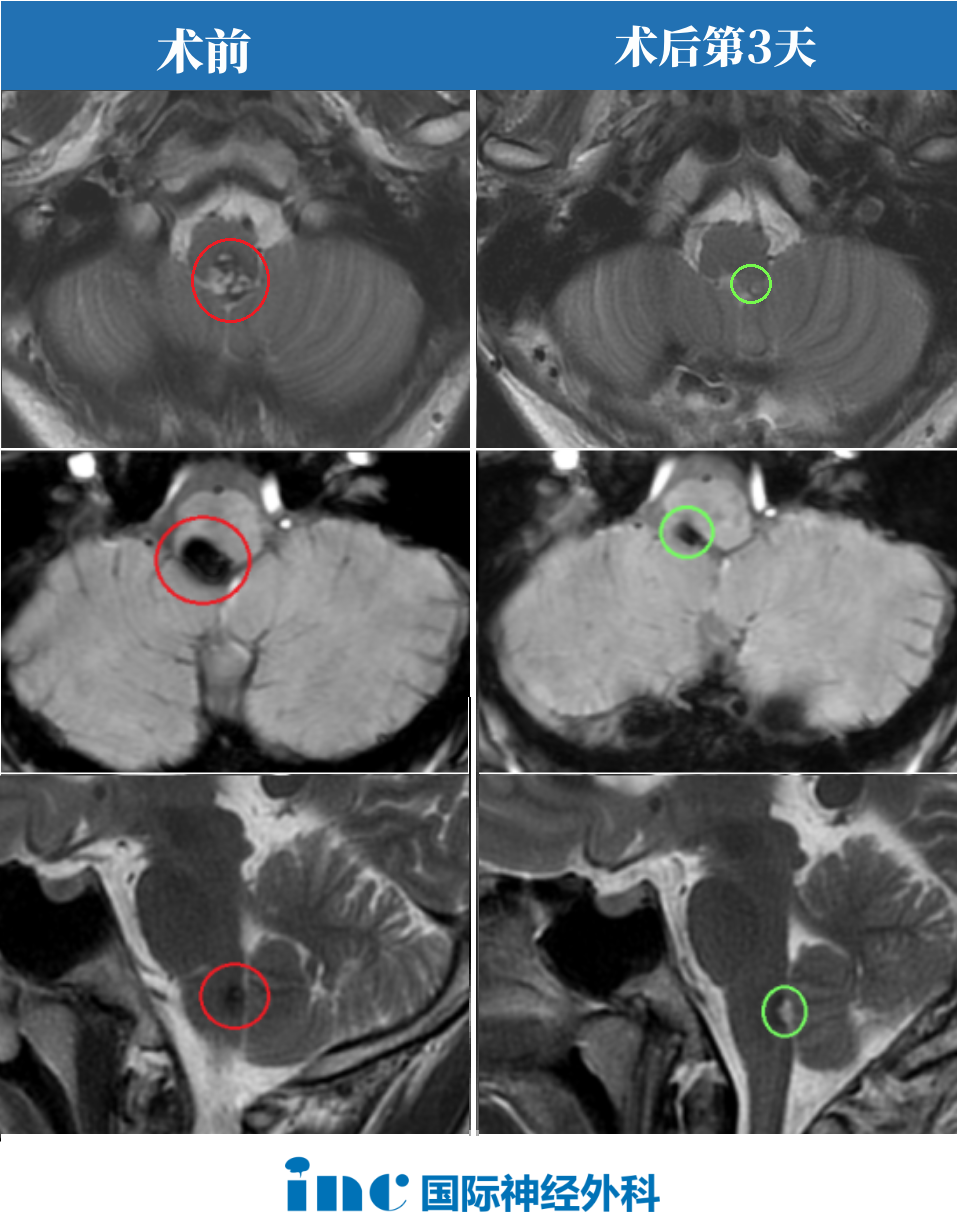

术前情况:20岁大学生,意识紊乱并逐渐恶化,左侧偏瘫,MRI显示脑干中脑出血,急性梗阻性脑积水。病变位于脑干腹侧中脑中线,体积10.7立方毫米,深度42.5毫米,肿瘤侧倾角11.6°(图A、B)。

手术入路:巴特朗菲教授根据患者病情、肿瘤生长及MRI影像特征,先行脑室引流术,随后采用双额骨瓣开颅、经基底纵裂入路完成病变全切。

术后情况:Maritta术后恢复顺利。意识和偏瘫症状迅速改善,脑积水消退。患者步行出院,3个月后随访无任何神经或认知功能障碍。术后MRI显示轴内血肿和血管病变完全切除(图C、D)。

图A、B显示术前MRI影像,确诊出血性中脑海绵状血管瘤。黄色虚线标示肿瘤深度(42.5毫米)。图C、D显示血管病变完全切除后的术后MRI,病灶全切,压迫占位效应解除,脑组织复位,未见手术损伤如脑出血或脑水肿。